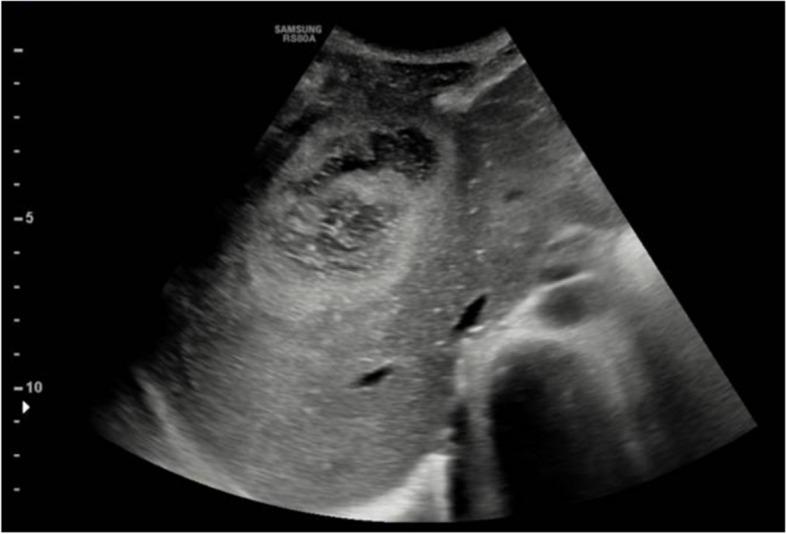

We report the case of a 15-year-old previously healthy boy diagnosed with both pulmonary empyema and subphrenic chest wall abscess caused by Aa. He was admitted to our Pediatric Emergency department for evaluation of a right mass associated with marked asthenia and dry cough. After radiological findings etiological diagnosis was made by culture of fluid drainage of pleural empyema. He started empirical antibiotic therapy with intravenous piperacillin/tazobactam, whose sensibility was confirmed by the antibiogram, then, for occurrance of hepatopathy it was switched to ciprofloxacin: the patient almost completely recovered after 6-month therapy.

我们报告了一例 15 岁既往健康的男孩,被诊断为 Aa 引起的肺脓胸和膈下胸壁脓肿。他因右肺肿块伴明显乏力和干咳而被收入我院儿科急诊。在影像学检查后,通过胸腔积液引流的培养进行了病因诊断。他开始接受经验性抗生素治疗,静脉注射哌拉西林/他唑巴坦,药敏试验证实了抗生素的敏感性,然后因出现肝损伤而改用环丙沙星:患者在 6 个月的治疗后几乎完全康复。